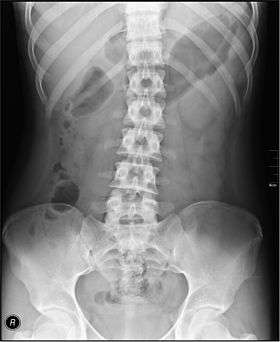

Abdominal X-rays may be used to visualise the large intestine.

Diseases affecting the large intestine may cause blood to be passed with stool, may cause constipation, or may result in abdominal pain or a fever. Tests that specifically examine the function of the large intestine include barium swallows, abdominal x-rays, and colonoscopy.[3]:913–915